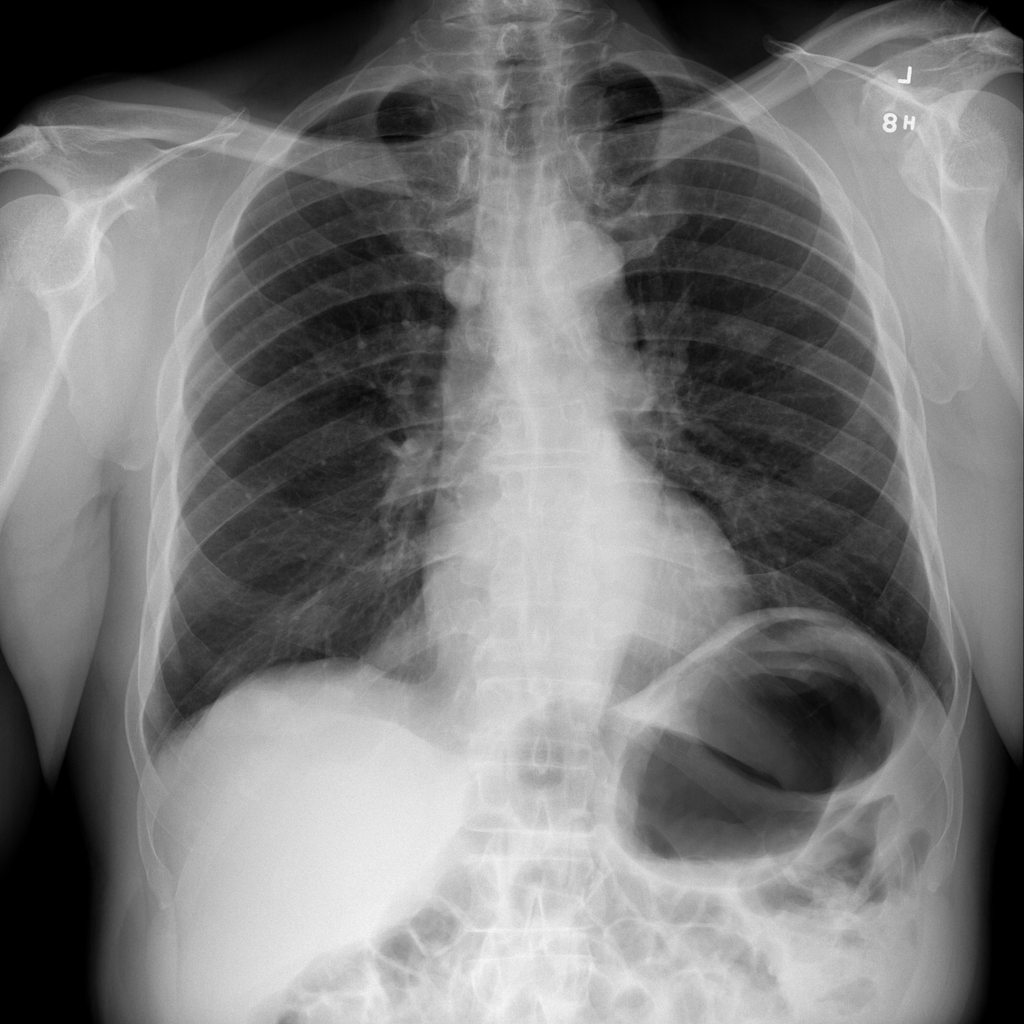

Showing up to 90 reference images for Emphysema.

PAT-C255 · IMG-000Emphysema

PAT-C255 · IMG-000

PA